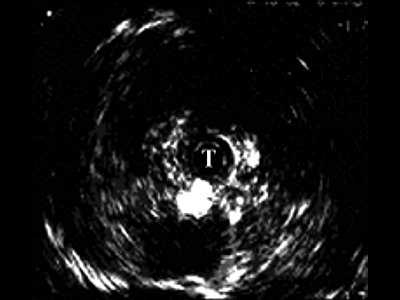

На рис. 6 а,б представлены ультрасонограммы в зоне стриктуры на границе мембранозного и простатического отделов. Определяются повышенной эхогенности участки фиброза, распространяющиеся за пределы уретры в парауретральную ткань. По мере проведения датчика определяется протяженность фиброзно-измененных тканей.

а) На границе мембранозного отдела, стрелка - участок склероза.

б) На границе простатического отдела.